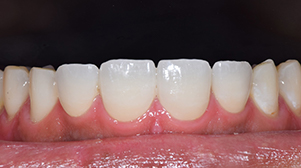

治療前

治療後

年齢・性別 52歳・女性

主訴 前歯をきれいにしたい

治療内容 右上1左1コア形成、仮歯作成、ジルコニアボンドクラウン形成

治療費 合計:335,500円

(内訳)

仮歯:2,500円×2

ジルコニアボンドクラウン:165,000円×2

(2022年4月現在)

治療期間 2ヶ月

治療のリスク・副作用 天然歯より硬いので嚙み合う歯が欠けてしまうことがある。

セルフケアを怠ると被せ物の内側が虫歯になることがある。